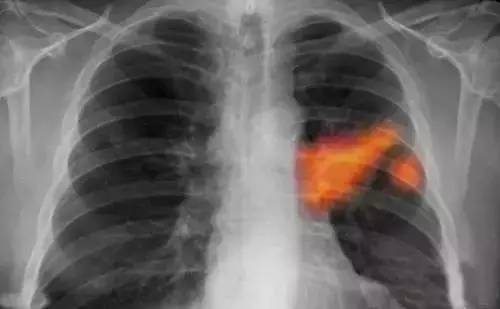

武漢肺癌最新動態顯示,研究、治療和科普工作取得重要進展。當地醫療機構和專家團隊不斷深入研究肺癌的發病機制,采用最新的治療技術,提高患者生存率。科普宣傳也加強,提高公眾對肺癌的認識,促進早期發現和治療。這些努力為肺癌患者帶來希望,展示了武漢在肺癌領域的積極進展。

武漢的科研團隊在肺癌的基因組學研究方面取得了重要突破,某研究團隊成功識別了數個與肺癌發生、發展密切相關的關鍵基因,這一發現為肺癌的精準治療提供了有力支持,該團隊還積極參與臨床試驗和新藥研發,與制藥公司緊密合作,推動多項針對肺癌的新藥進入臨床試驗階段,部分新藥已顯示出顯著的療效,為肺癌患者帶來了新的希望。

在手術治療方面,武漢的醫療機構引入了先進的手術設備和技術,如機器人手術系統,通過這一技術,醫生和醫療團隊能夠更精準、更安全地進行肺癌手術,大大提升了手術成功率,針對肺癌的綜合治療,武漢的專家團隊積極優化治療方案,結合患者的具體情況,采用免疫治療、靶向治療等新型治療方法,為患者提供更加個性化的治療方案,某肺癌患者經過綜合治療,成功戰勝病魔的案例便是其中的亮點。